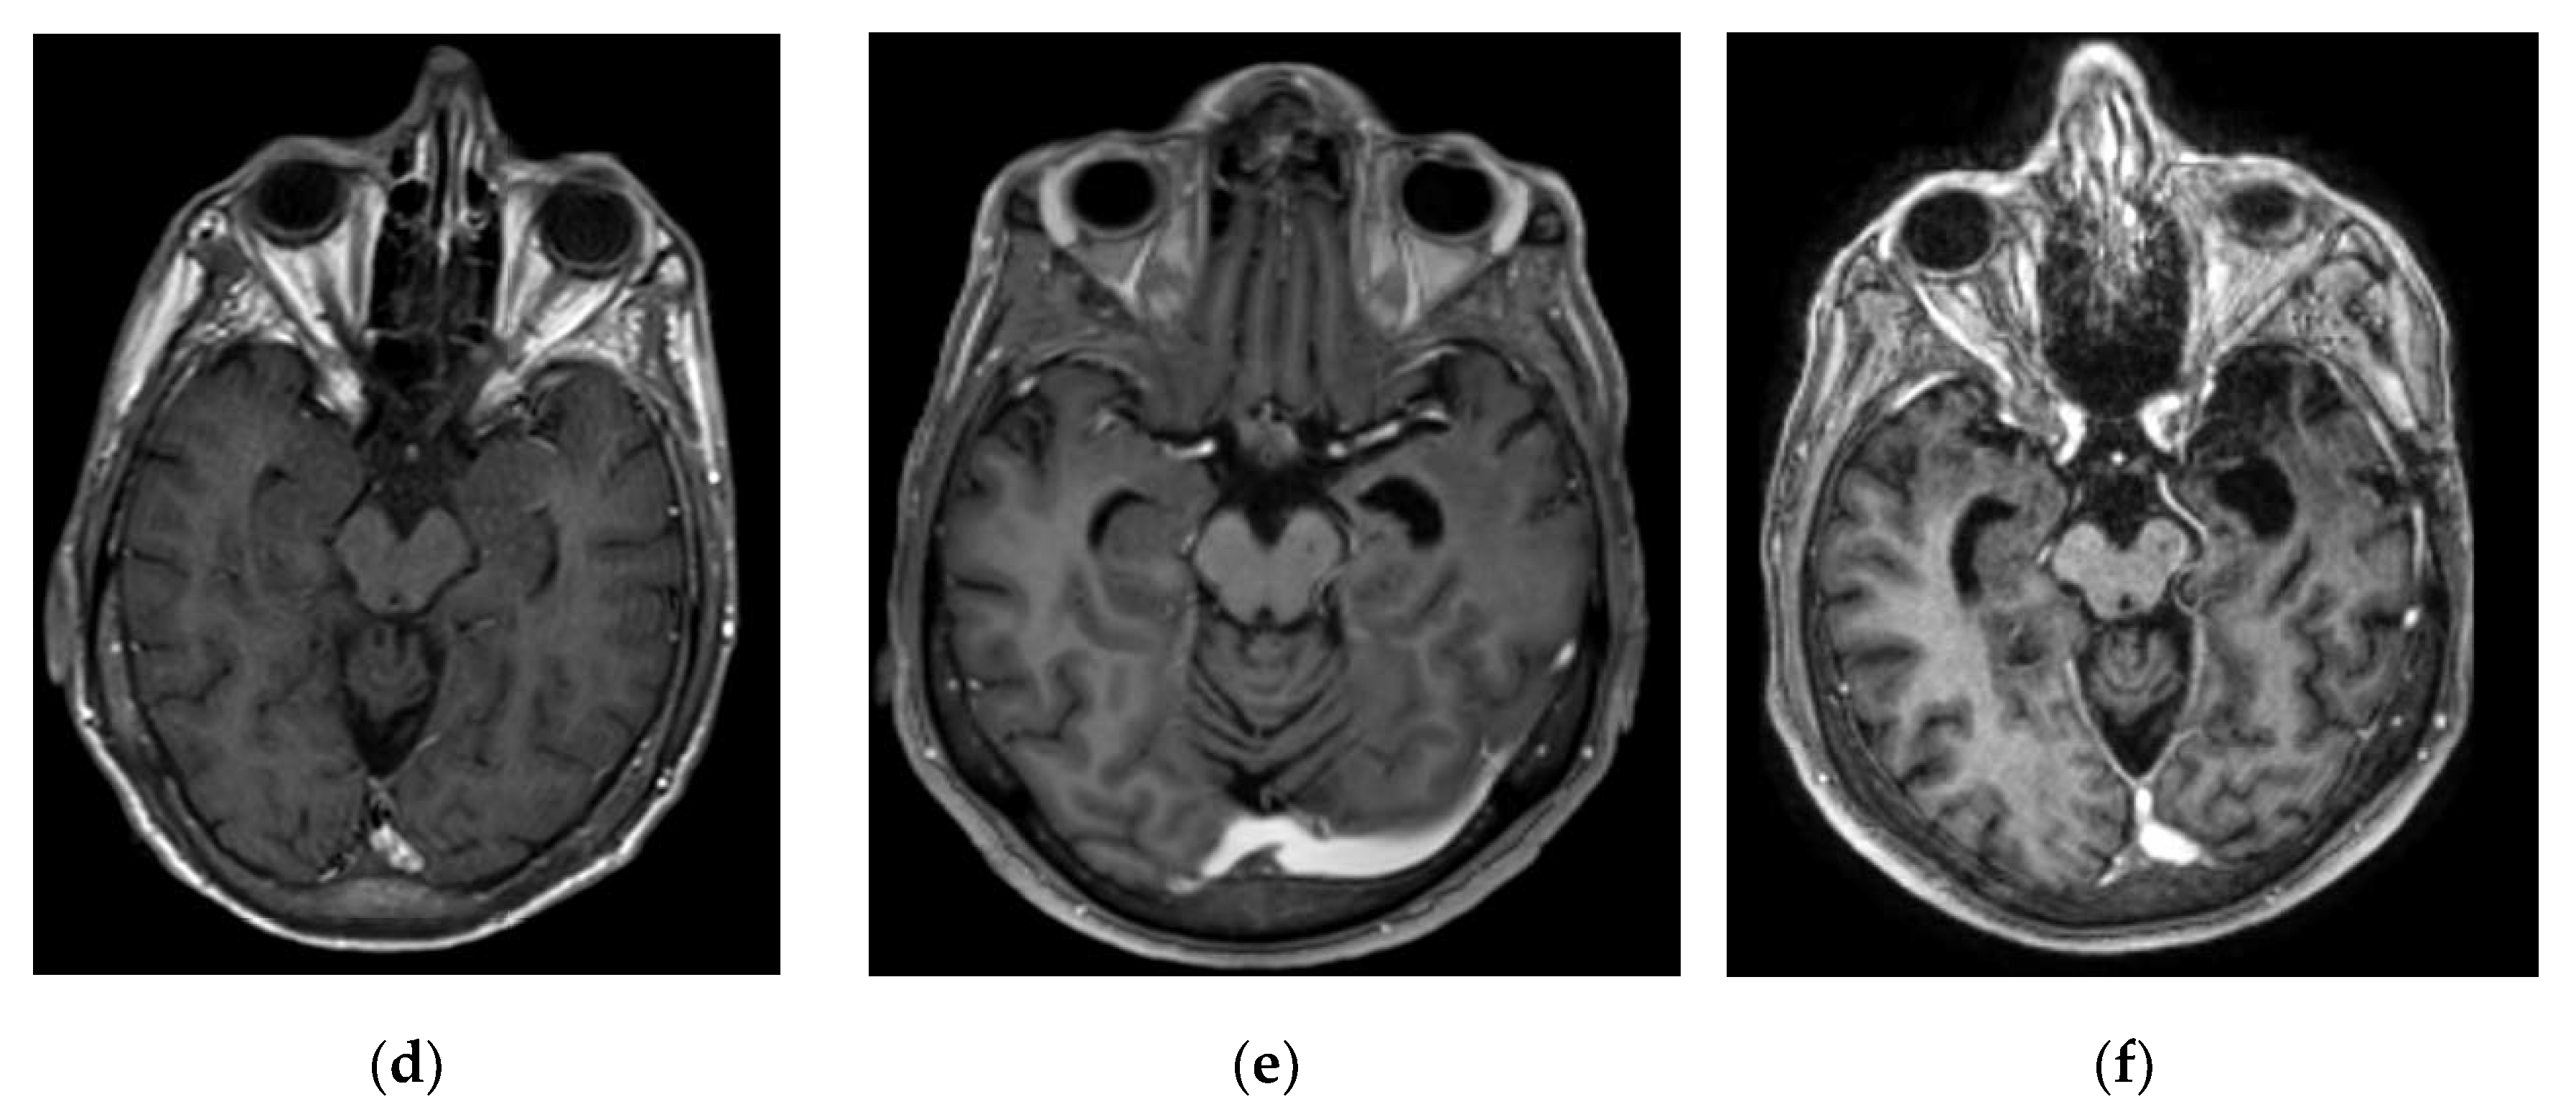

1.1. Admission 1

1.2. Admission 2

1.3. Admission 3